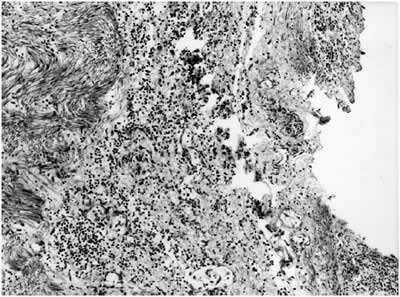

Histologically, all the layers of the abomasum showed severe oedema. The abomasal mucosa showed multiple ulcers and haemorrhage (figure 2). The submucosa showed diffuse infiltration of inflammatory cells, predominantly neutrophils, lymphocytes and plasma cells. Large amounts of thick, short Gram-positive rods were observed in the mucosa and submucosa. Large areas of necrosis surrounded by a ring of inflammatory cells and haemorrhage were observed in the cecum of the animal that showed gross lesions in this organ. Many arterioles in the submucosa of the cecum showed thrombi.